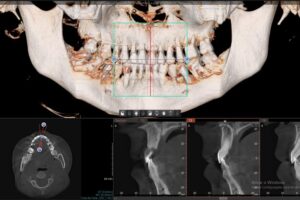

Virtobot atualizou o anterior. Atualmente com sua nova versão atualizada, o Virtobot melhorou a precisão da biópsia e está focado em agilizar o fluxo de trabalho e aumentar o nível de automação. Recentemente, técnicas mais avançadas de digitalização 3D foram introduzidas, permitindo imagens multiespectrais de corpo inteiro. A imagem utilizou fotogrametria multiespectral de 365 nm a 960 nm usando uma câmera digital com melhorias nas fontes de luz ultravioleta e infravermelha próxima e filtros de lente para revelar possíveis traços dentro do corpo. Fluidos corporais, hematomas, etc. Para detectar cadáveres através da arcada dentária (Crânio Facial), é utilizada outra ferramenta de radiologia forense a virtual autópsia dentária, a mesma foi projetada para melhor atender às necessidades dos setores judicial e criminal.

O Instituto de Identificação Humana da Universidade de Turim e o Gabinete de Assuntos Médicos e Jurídicos lançaram um projeto de pesquisa em 2020 com base na hipótese de que o processo de identificação de corpos não identificados deve sempre seguir os melhores protocolos para esclarecer a identificação de corpos, disse,( Nuzzolese, E. 2021). deve sempre incluir um exame odontológico completo para complementar e documentar a autópsia mesmo quando um dentista forense não estiver no local. Além disso, ferramentas virtuais em medicina e odontologia também podem ser utilizadas em medicina forense, especialmente para identificação pessoal,após a pandemia de COVID-19 e o risco potencial de infecção obrigou as instituições forenses a realizar autópsias virtuais sem comprometer as informações técnicas fornecidas pelo dentista forense. Atualmente, poucos departamentos ao redor do mundo reconhecem a viabilidade da autópsia tele dental, mas algumas instituições oferecem consultas remotas em odontologia legal para identificação pessoal ou oferecem este serviço por motivos humanitários. O projeto reúne temas de pesquisa como patologia, odontologia, antropologia e arqueologia, sob a égide dos direitos humanos dos mortos e da odontologia forense humanitária. O termo VIRDENTOPSY é uma combinação dos termos “virtual” e “anatomia dentária”. Esta é uma marca registrada de um site dedicado a fornecer avaliação odontológica forense remota de dados dentários post-mortem de restos mortais não identificados. O uso de radiografias em odontologia legal visa facilitar a identificação de corpos por meio do exame de detalhes anatômicos que podem ser utilizados como parâmetros. Isso inclui o formato dos dentes e raízes, dentes ausentes e existentes, raízes remanescentes, dentes supranumerários, fricção e desgaste e fraturas radiculares, grau de

reabsorção óssea devido à periodontite, lesões ósseas, diastema, formato e linha da cavidade, cáries, terapia endodôntica, pinos intrarradiculares e próteses dentárias. (Eastman, R., Raibley, et al 1982).

O processo de identificação de restos mortais não identificados deve respeitar os mais elevados padrões forenses e deve incluir sempre a recolha de todos os dados de identificação post-mortem. A tomografia cone beam(TCFC) é um método radiológico caracterizado por alta resolução espacial e baixa dose de radiação, adequados para diagnóstico prognóstico quando são identificados resíduos desconhecidos. Esses métodos permitem obter imagens precisas e detalhadas das estrutura dentárias e craniofaciais, essenciais para a identificação post mortem de indivíduos.Este processo requer a comparação de pessoas desaparecidas correspondentes com dados ante-mortem documentadas e a reconciliaçãofinal de todos protocolos(Da Luz Silva, W., Dias, R. S., Vergara, C. S., & De Sá, L.

- 2023). Neste contexto, uma autópsia dentária completa e uma avaliação adicional de todos os achados dentários por um dentista legista são essenciais para obter um perfil biológico geral e um exame geral.Simples exames dentários e recolha de dados dentários sem avaliação por especialistas em odontologia forense e identificação de vítimas não podem dar um contributo tangível para uma identificação pessoal atempada e eficaz. É necessária uma recolha e análise mais abrangentes de dados post-mortem quando se consideram os fenómenos migratórios Em Itália, o Projecto Migrantes Desaparecidos estima que houve 124 mortes e desaparecimentos de migrantes desde 2014, e mais de 60 dessas vítimas não foram identificadas As avaliações odontológicas forenses, por outro lado, limitam-se a exames odontológicos de não vítimas.Dentistas forenses experientes parecem estar rotineiramente envolvidos as aplicações de anatomia virtual em odontologia forense incluem a coleta de dados dentários e a comparação de ortopantomografias post-mortem O processo de virdentopsia não apenas integra a dissecção virtual na prática da odontologia forense, mas também depende de vídeo 2D e 3D, fotografia e fotogrametria, bem como imagens de raios X e tomografia computadorizada.documentação.

A dissecção virtual permite que os dentistas examinem mandíbulas e dentes sem realizar uma dissecação dentária tradicional ao envolver dentistas remotos de vários países sem a necessidade de estarem fisicamente presentes, a Virdentopsia expande os horizontes desta abordagem virtual e tem o potencial de se tornar o padrão para todos os restos mortais não identificados recuperados(Nuzzolese, E. 2021).Uma radiografia típica é baseada na comparação de radiografias ante-mortem e post-mortem mantidas em um consultório ou centro de pesquisa odontológica. Esses raios X fornecem muitas informações sobre a pessoa.